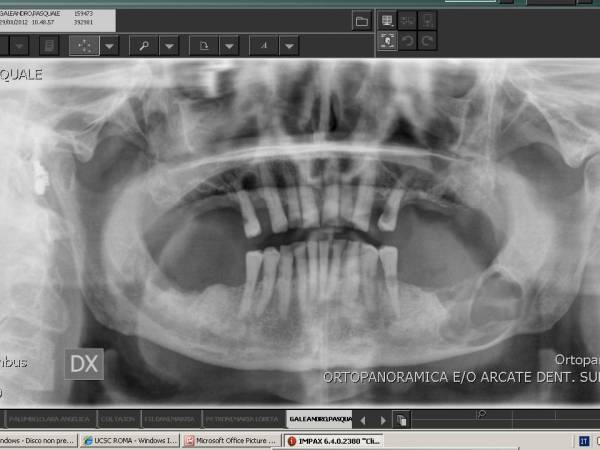

Gli elementi dentali cominciano a formarsi dai 10 12 anni ed in ortopanoramiche eseguite in quell´età già si possono evidenziare le gemme dentali in via di formazione. Le gemme crescono nel contesto dell´osso ma data la loro localizzazione nella porzione più posteriore delle arcate dentali e formandosi con pochissimo spazio a disposizione possono orientarsi in maniera erronea avendo successivamente limitata o completamente abolita la possibilità di emergere in arcata.

La crescita dei denti del giudizio dovrebbe essere monitorata attraverso una RX ortopanoramica a cominciare dai 16-17 anni. Se si evidenziano anomalie di crescita conviente estrarre tali elementi prima che le radici completano la loro formazione. Generalmente conviene togliere i dneti del giudizio che non riescono ad emergere per via della loro inclinazione tra i 16 ed i 20 anni.